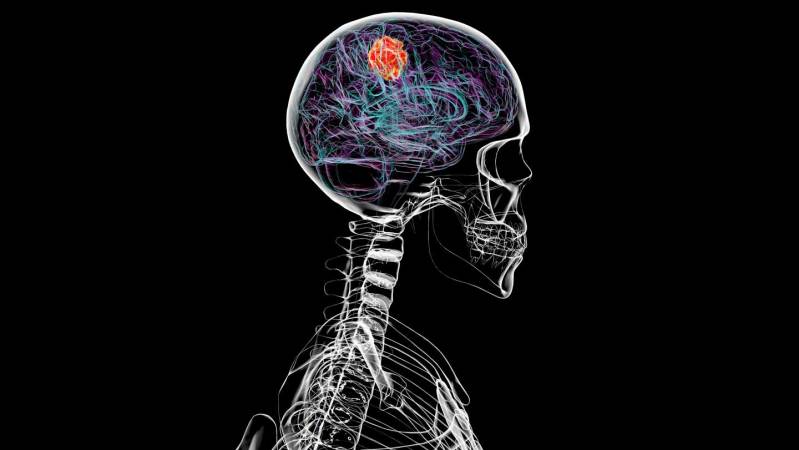

Glioblastoma doesn’t just affect the brain. It also erodes bones in the skull and changes the composition of immune cells in skull marrow.Glioblastoma doesn’t just affect the brain. It also erodes bones in the skull and changes the composition of immune cells in skull marrow. Read More